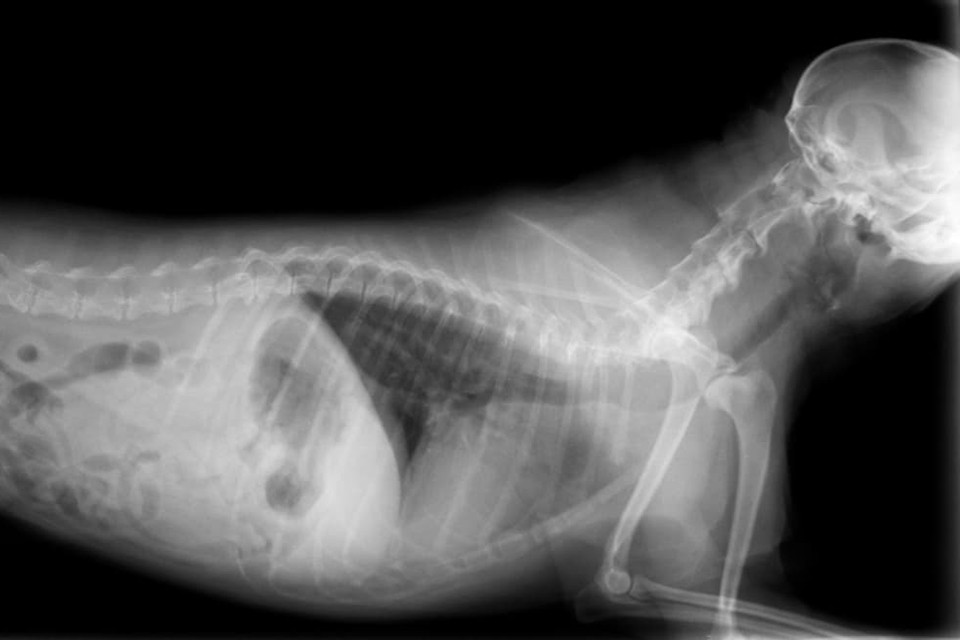

Hayvanları tedavi etmek için dijital röntgenlerin kullanılması, hayvan sağlığını tehdit eden birçok hastalığın teşhis edilmesini kolaylaştırmıştır. Daha yüksek maliyete sahip olan ithal X-ray makinesi, normal X-ray makinelerinden görüntülerin bilgisayara aktarılabilmesi ve 5.000 kat büyütülebilmesi açısından farklılık gösteriyor. Hayvanların iç organlarının ve kemiklerinin kalınlığını ölçebilen aletler sayesinde birçok hastalığın erken teşhisi gerçekleşebiliyor. Yeni dijital röntgenler sayesinde kedi ve köpeklerde yaygın olan büyümüş kalp de rahat bir şekilde tespit edilebilir. Köpeklerde kalça çıkığının sıklığı da bu cihazla ölçülebilir. Ayrıca tüm bu röntgen cihazlarının teknik özellikleri sayesinde veteriner hekimler anlaşılmayan konuları meslektaşlarıyla e-posta yoluyla tartışabilirler.

7 gün 24 saat hizmet vermekte olan kliniğimizde röntgen – dijital röntgen kapsamında görüntüleme için CR (Bilgisayarlı X-ray) ekipmanı ve yüksek frekanslı X-ray ekipmanı kullanıyoruz. Türkiye Atom Enerjisi Kurumu onaylı bir röntgen cihazı ile ne siz ne de evcil hayvanınız radyasyona maruz kalmaz. Sıradan X-ray cihazlarına göre birçok avantajı olan cr sistemi, evcil hayvanınızı bilgisayar ekranından kucağınıza rahatlıkla almanızı sağlar. Sadece 1 dakika içinde görüntüleri görüntüleyebilirsiniz.